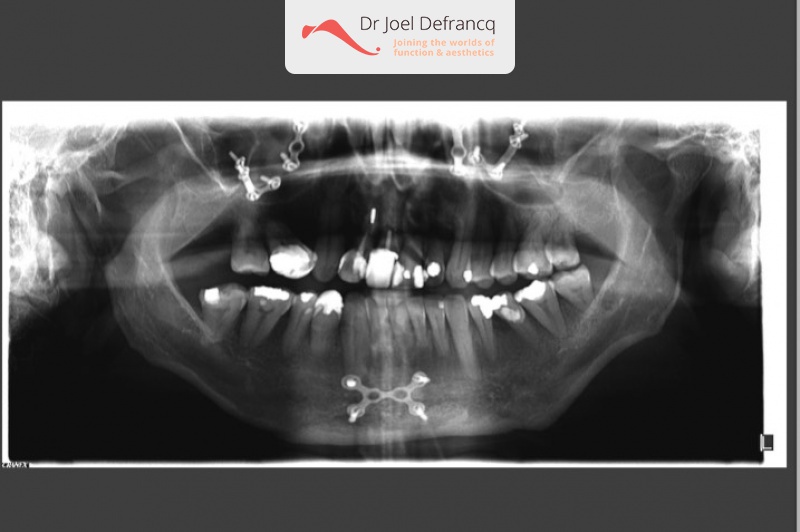

Kaakchirurgie

- Verlenging onderkaak (BSSO)

- Verlenging bovenkaak (Le Fort I)

- Rotatie bovenkaak

- Onderkaak rotatie

- Kinchirurgie

Behandeling tandheelkundige implantaten

- Vaste tanden op implantaten (bovenkaak)